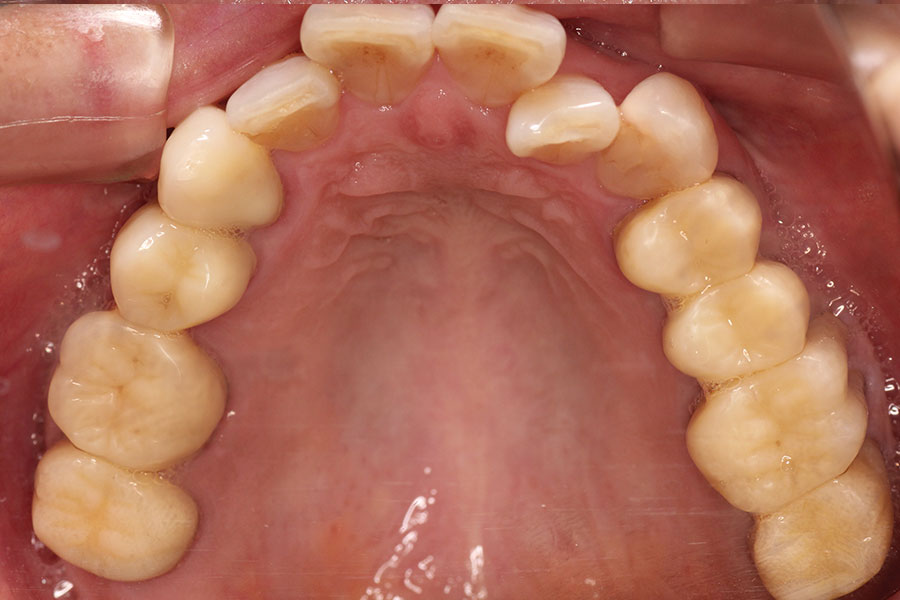

Before -上顎-

After -上顎-

| 施術内容 | 金属アレルギー予防を目的に、金属フリーの自費補綴へ変更。適合性・清掃性・審美性の向上が得られています。 |

|---|---|

| 治療期間 | 約4ヶ月 |

| 費用 | オールセラミッククラウン 264,000円 オールセラミックインレー ハイブリットインレー 275,000円 |

| リスク・副作用 | 治療にともない、歯の破折や歯質の削合、場合によっては抜歯が必要となることがあります。また、金属や補綴物を除去する際に、完全に除去できない場合もあります。 |